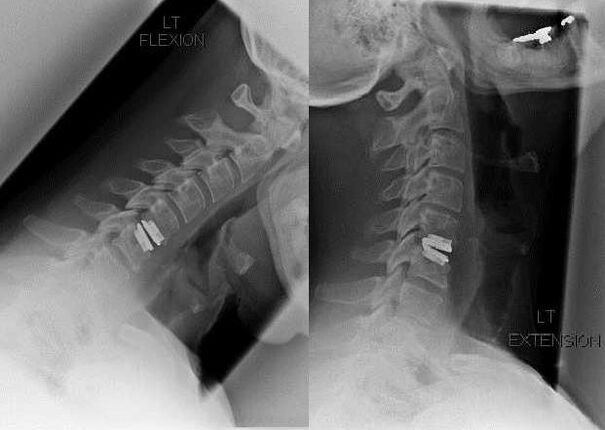

As indicacións para a intervención cirúrxica inclúen a ineficacia do tratamento conservador, así como as complicacións da osteocondrose cervical, por exemplo, a mielopatía discoxénica, a síndrome da arteria vertebral e a síndrome radicular. Para descomprimir a medula espiñal, os vasos sanguíneos e as raíces da columna, realízanse as seguintes operacións: